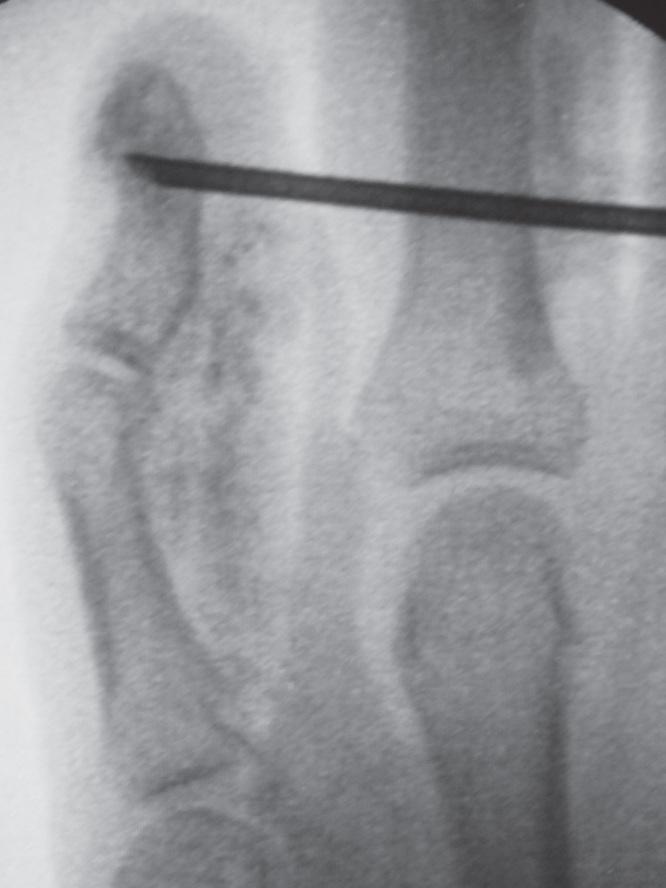

Vascular malformations of bone are complex lesions that can cause deformity and pain. A combined soft tissue and intraosseous venous malformation of the left thumb in a girl was treated with two sessions of ethanol sclerotherapy using a bone marrow aspiration needle under fluoroscopic guidance.

骨血管畸形是一种复杂的病变,可导致畸形和疼痛。一名女孩左拇指的软组织和骨内静脉联合畸形,在透视引导下使用骨髓穿刺针进行了两期乙醇硬化治疗。